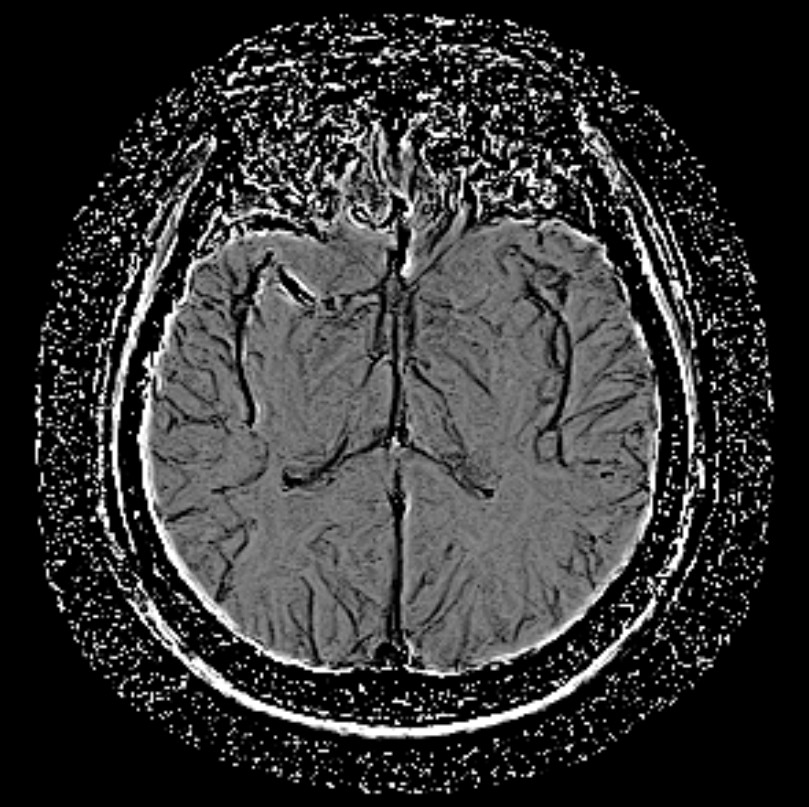

颅脑-T2WI